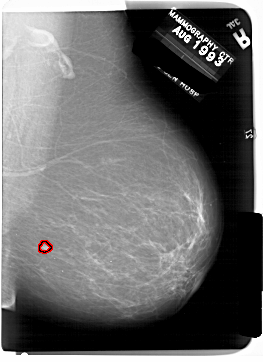

A_1857_1.RIGHT_MLO

RIGHT_MLO LINES 6871 PIXELS_PER_LINE 4981 BITS_PER_PIXEL 12 RESOLUTION 43.5 OVERLAY

FILE: A_1857_1.RIGHT_MLO.OVERLAY

TOTAL_ABNORMALITIES 1

ABNORMALITY 1

LESION_TYPE MASS SHAPE IRREGULAR MARGINS ILL_DEFINED

ASSESSMENT 4

SUBTLETY 3

PATHOLOGY BENIGN

TOTAL_OUTLINES 1

BOUNDARY